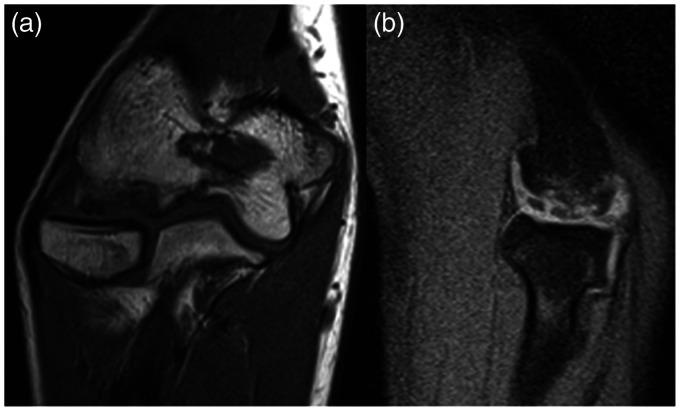

Interobserver reliability of the classification of capitellar osteochondritis dissecans using magnetic resonance imaging.

(1) To determine the interobserver reliability of magnetic resonance classifications and lesion instability criteria for capitellar osteochondritis dissecans lesions and (2) to assess differences in reliability between subgroups.

Magnetic resonance images of 20 patients with capitellar osteochondritis dissecans were reviewed by 33 observers, 18 orthopaedic surgeons and 15 musculoskeletal radiologists. Observers were asked to classify the osteochondritis dissecans according to classifications developed by Hepple, Dipaola/Nelson, Itsubo, as well as to apply the lesion instability criteria of DeSmet/Kijowski and Satake. Interobserver agreement was calculated using the multirater kappa (k) coefficient.

Interobserver agreement ranged from slight to fair: Hepple (k = 0.23); Dipaola/Nelson (k = 0.19); Itsubo (k = 0.18); DeSmet/Kijowksi (k = 0.16); Satake (k = 0.12). When classifications/instability criteria were dichotomized into either a stable or unstable osteochondritis dissecans, there was more agreement for Hepple (k = 0.52; p = .002), Dipaola/Nelson (k = 0.38; p = .015), DeSmet/Kijowski (k = 0.42; p = .001) and Satake (k = 0.41; p < .001). Overall, agreement was not associated with the number of years in practice or the number of osteochondritis dissecans cases encountered per year (p > .05).

One should be cautious when assigning grades using magnetic resonance classifications for capitellar osteochondritis dissecans. When making treatment decisions, one should rather use relatively simple distinctions (e.g. stable versus unstable osteochondritis dissecans; lateral wall intact versus not intact), as these are more reliable.